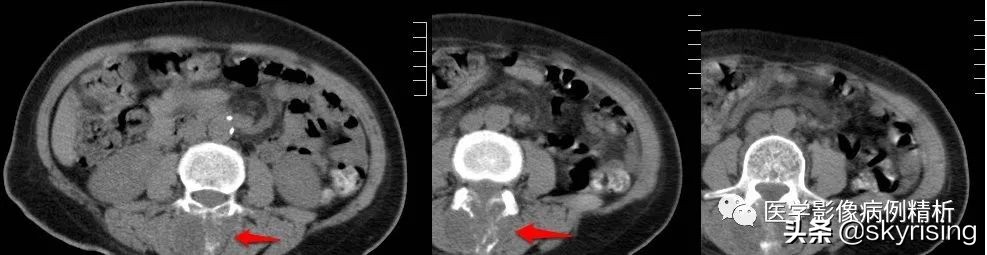

CT 平扫

CT:红色箭头所示为腰3椎体附件包括棘突、双侧椎弓根骨质呈溶骨性破坏, 其内见多发点状、条形骨瘠残留,相应部位见团块状稍低密度影,大小约3.5cmx2cm,边界欠清,密度欠均匀。